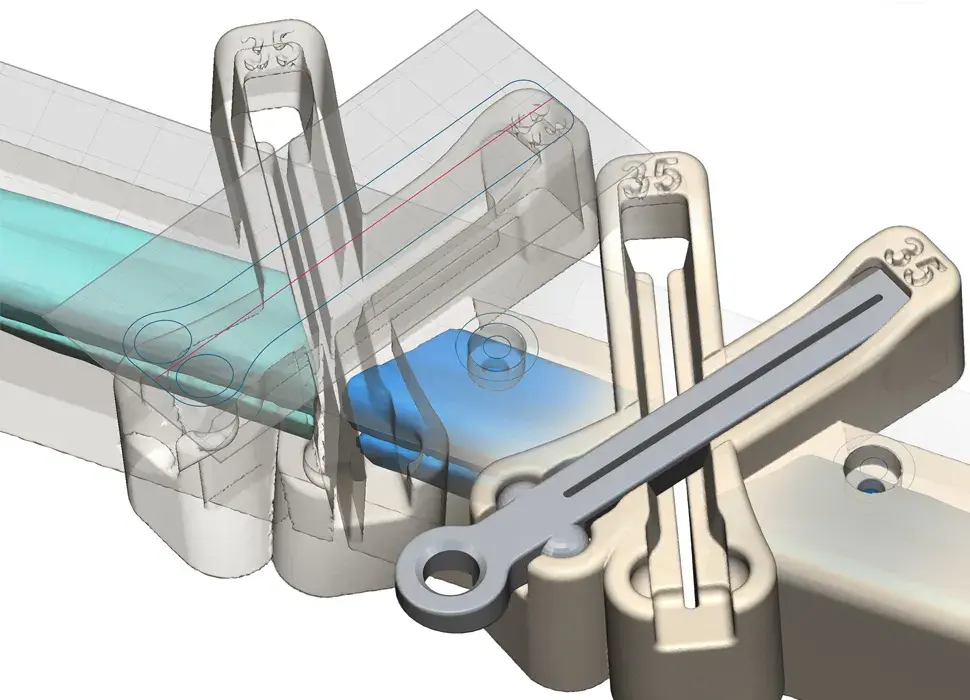

3D Systems' VSP® surgical planning solutions for craniomaxillofacial (CMF) applications received FDA clearance as a service-based approach to personalized surgery over 10 years ago.

3D Systems and Stryker Corporation have partnered to provide surgeons with best-in-class products and services for craniomaxillofacial surgeries. As a leader in personalized healthcare solutions, 3D Systems has planned and delivered devices for more than 140,000 patient-specific cases. The Stryker Craniomaxillofacial business specializes in providing patient-specific options and innovative solutions that help drive efficiencies in surgical suites. The combination of Stryker’s specialized team and advanced implants with 3D Systems' cutting-edge 3D printing technologies and expert consulting services positions both companies to provide a superior level of service to healthcare professionals who use these revolutionary solutions.